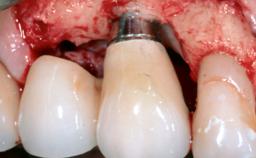

Peri-Implant Mucositis Associated with Misfit of a Cemented Restoration

A 37-year-old male patient was referred to the Department of Periodontology at the University of Bern, Switzerland, by a private dentist. Tooth 21 had been lost due to trauma and had been replaced with an implant and a cemented single crown. The tapered-effect tissue-level implant had a diameter of 4.1 mm, a length of 12 mm, and a sandblasted and acid-etched (SLA) surface (Straumann Dental lmplant System; Institut Straumann AG, Basel, Switzerland). The metal-ceramic crown had been cemented permanently, leaving a submucosal gap between the implant shoulder and the crown margin. Absence of marginal bone loss apical to the polished transmucosal neck of the implant could be observed .